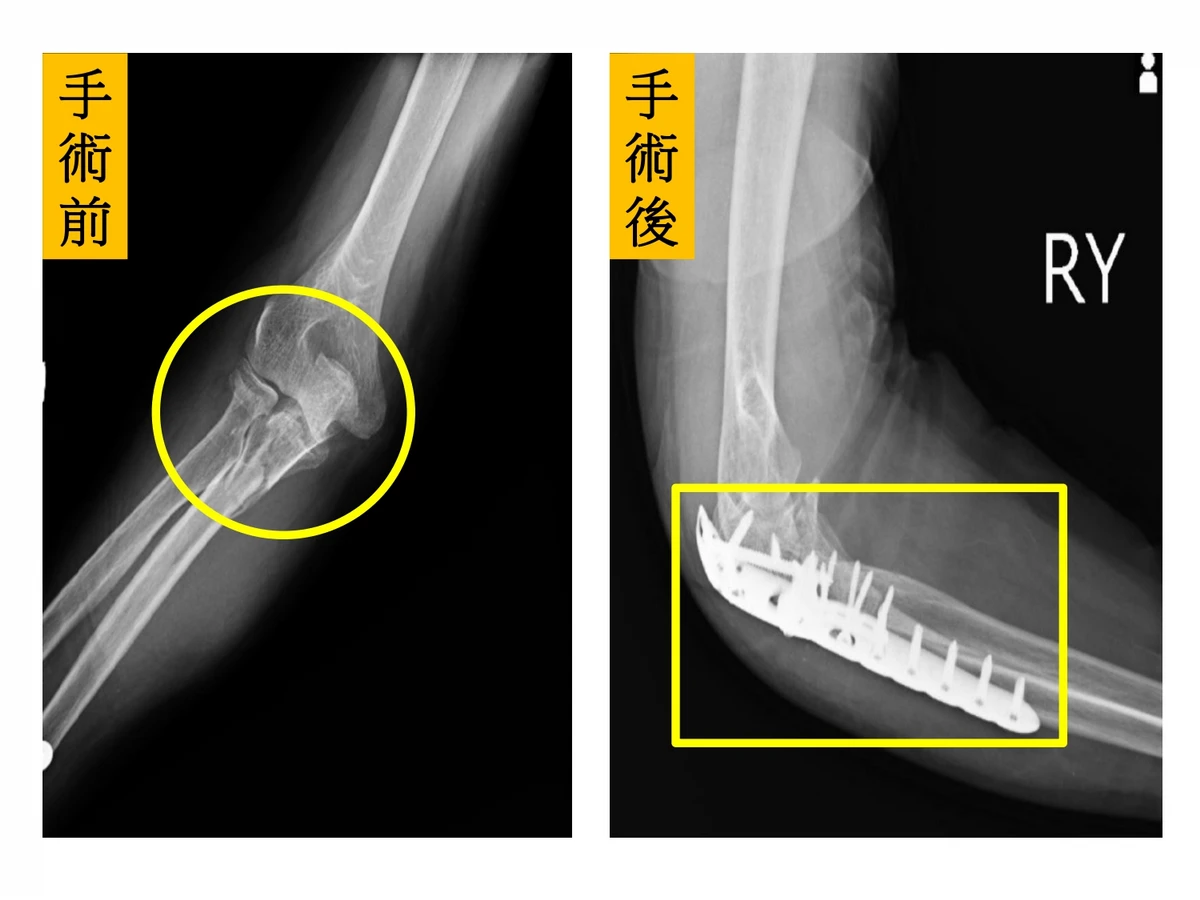

一名70歲陳先生在家中不小心跌倒,左手手肘直接撞到地上,手肘嚴重變形、劇烈疼痛、活動困難,家人趕緊將陳先生送到醫院急診,X光發現患者手肘呈現粉碎性骨折還有手肘關節脫臼。急診醫師將手肘關節復位後,再安排電腦斷層進行檢查,發現這是令國內外骨科醫師都十分頭痛的「手肘恐怖三聯症」(Terrible Triad Injury of Elbow)。

後續,醫師除了安排橈骨頭人工關節置換手術,也進行尺骨冠狀突骨折固定及手肘外側副韌帶(Lateral collateral ligament ,LCL)修補手術。手術後陳先生不僅可以開心比「讚」和「OK」,2個月後手肘關節已活動自如,生活終於恢復正常。

術前X光片顯示病人手肘呈現粉碎性骨折(圓圈處,圖左);術後病人手肘關節已活動自如,生活恢復正常(方框處,圖右)。(圖片來源:仁愛長庚合作聯盟醫院)